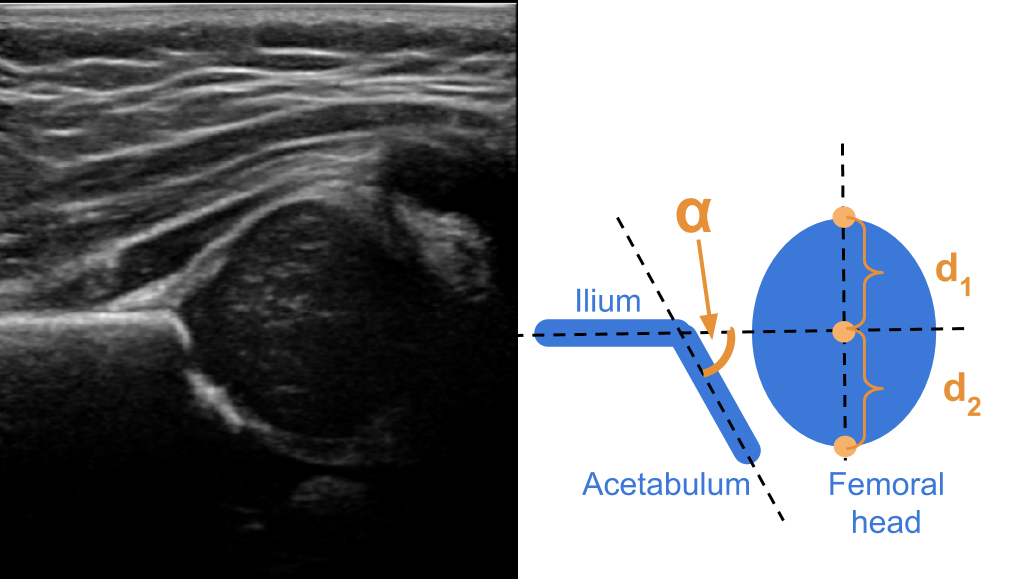

4.3 Experiment 3: Fatty Liver

The machine learning task is to produce a model that predicts if an ultrasound image of the liver (see Figure 5, right) should be diagnosed as fatty, or normal. We used a private dataset that contains 505 images, with labels made by an expert radiologist. We placed 353 (70%) in the training set, and the remaining 152 in the hold out set. The percentage of normal cases in both sets was 62%.

Refer to caption

Figure 5: Typical images used for the diagnosis of glaucoma (left) and fatty liver (right).

4.4 Experiment 4: Glaucoma

Here, we wanted to learn a model that classifiers the fundus image of a retina (Figure 5, left) as healthy, or as suspicious of glaucoma. We used the publicly available dataset RIM-ONE r3 [4], which contains 85 images classified as normal, and 74 as suspects of glaucoma. We used 70% of the data for training purposes, while the remaining 30% was used as hold-out set. We kept the same healthy over glaucoma ratio in both datasets. Besides the diagnosis, which we used as ground truth, the dataset contains the masks of the disc and the cup masks of the optic nerve.